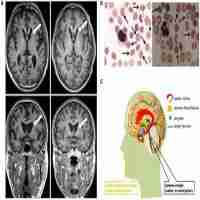

| Abstract | Mutations in VPS13A cause chorea-acanthocytosis (ChAc), an autosomal recessive neurodegenerative disorder. VPS13A is located in a tail-to-tail arrangement with GNA14 on chromosome 9q21. ChAc shows substantial allelic heterogeneity, with no single VPS13A mutation causing the majority of cases. We examined 11 patients in four French Canadian ChAc pedigrees for mutations in VPS13A. Affected members of three families were homozygous for a 37-kb deletion of the four terminal exons of VPS13A (EX70_EX73del). This deletion also encompasses the two terminal exons of GNA14. Two affected females in family 4 were homozygous for the splicing mutation 4242+1G>T. Remarkably, the affected males in this highly consanguineous pedigree were compound heterozygotes for EX70_EX73del and 4242+1G>T. PCR analysis of the deletion breakpoint junction revealed that an additional patient with French Canadian ancestry was heterozygous for the EX70_EX73del allele. The identification of a common 9q21 haplotype associated with EX70_EX73del in at least four apparently unrelated ChAc families implies that ChAc shows a founder effect in French Canadians, and that routine testing for EX70_EX73del in suspected ChAc cases may therefore be worthwhile in this population. The deletion breakpoint PCR described here will enable rapid identification of both homozygous and heterozygous carriers of EX70_EX73del. |